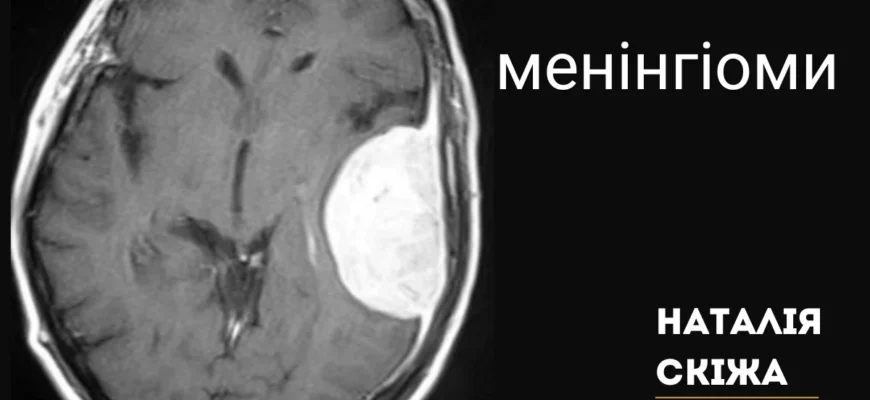

Що таке менінгіома?

Менінгіома — це тип пухлини головного або спинного мозку, яка походить з оболонок мозку. Як це? Уявіть тістечко з кремом усередині — оболонки це крем, що покриває ваш мозок. Зазвичай, ці пухлини доброякісні, але можуть викликати значні проблеми через їх розташування.